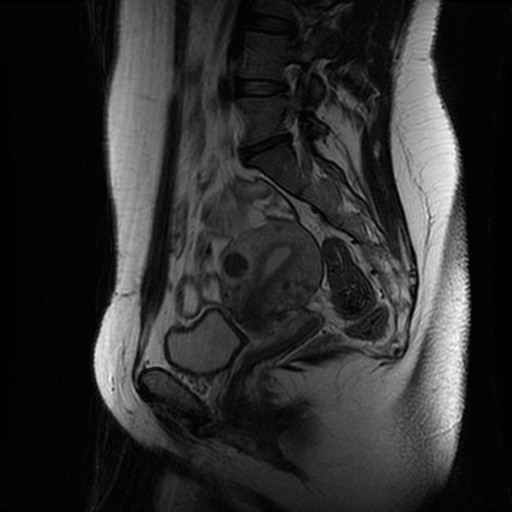

Lage Wervel Zuil